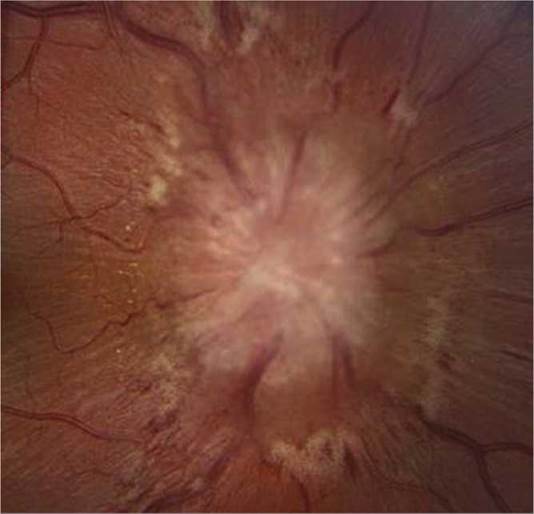

3. Dilated fundus examination: Search for chorioretinitis, papillitis, and uveitis.